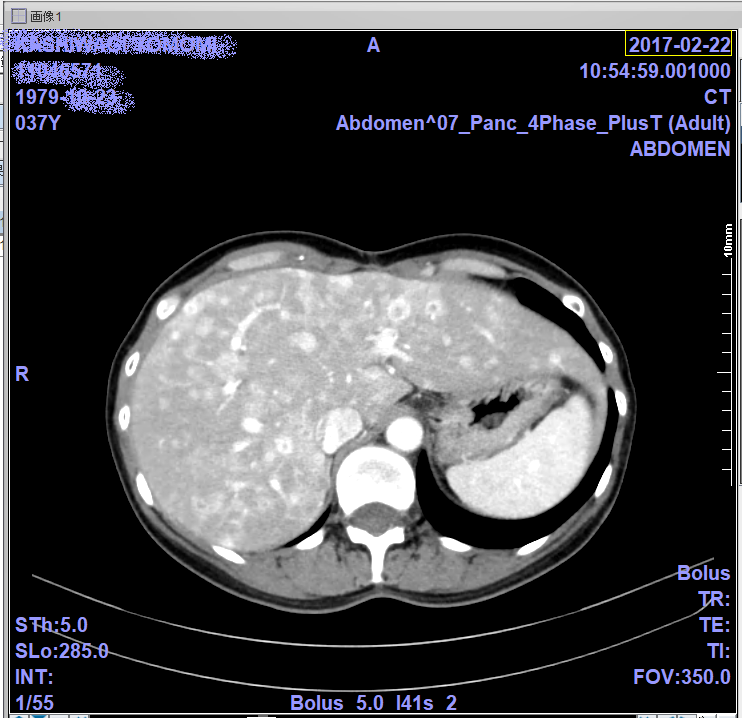

2月のCTとオクトレオスキャンの画像。

これが無治療だと半年で肝不全なっちゃう?肝臓らしいよ。

ちょっと肝臓腫れてるらしいけど、わからないね…

わかるかな?CTは白いやつが全部腫瘍。

オクトレオスキャンは光ってるやつ(二枚目の大きい濃いオレンジは違うよ)

参考にどうぞ。